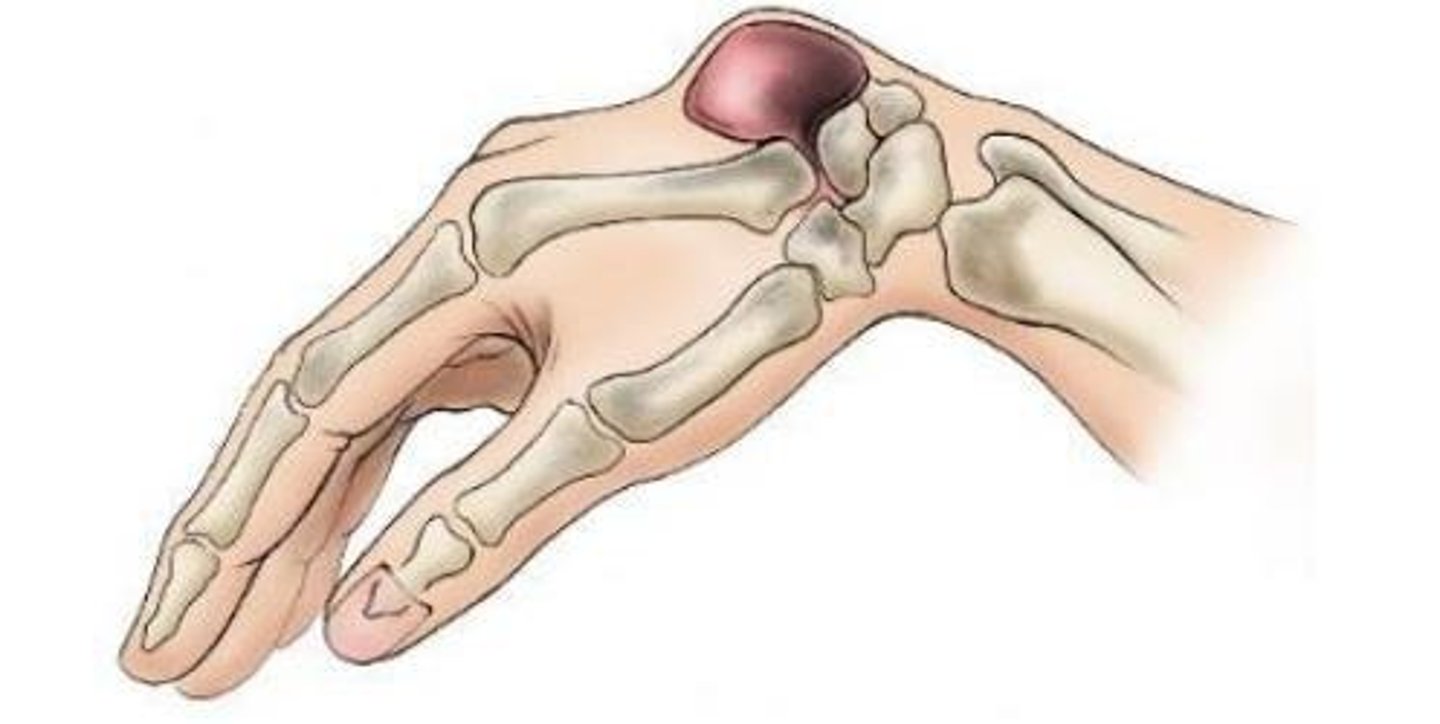

Dorsal Ganglion Cyst

Aka the "Bible bump"

Multifactorial pathogenesis: tissue stress, degeneration, underlying joint conditions

Originate from the dorsal wrist joint capsule fibers or dorsal fibers of the SL ligament

Presentation: Dorsal wrist pain when weightbearing in wrist extension